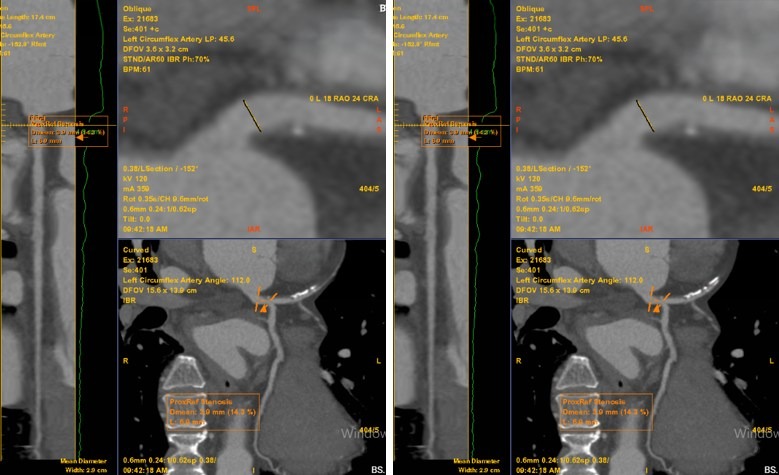

| Phim chụp tổn thương của bệnh nhân. |

Kết quả chụp MSCT phát hiện mảng xơ vữa hỗn hợp gây hẹp khoảng 60-70% đoạn LAD1–2, được phân loại CAD-RADS 3. Từ đó, bệnh nhân được chẩn đoán xác định mắc bệnh mạch vành mạn tính do xơ vữa. Các bác sỹ đã xây dựng phác đồ điều trị nội khoa, tập trung kiểm soát chặt chẽ các yếu tố nguy cơ tim mạch và điều trị dự phòng biến cố.

Việc chẩn đoán sớm bệnh mạch vành có ý nghĩa quan trọng trong phòng ngừa biến chứng. Hiện nay, chụp CT mạch vành là phương pháp không xâm lấn, cho phép đánh giá chính xác mức độ hẹp mạch, đặc điểm mảng xơ vữa và nguy cơ biến cố tim mạch, từ đó giúp bác sỹ xây dựng phác đồ điều trị phù hợp cho từng bệnh nhân.